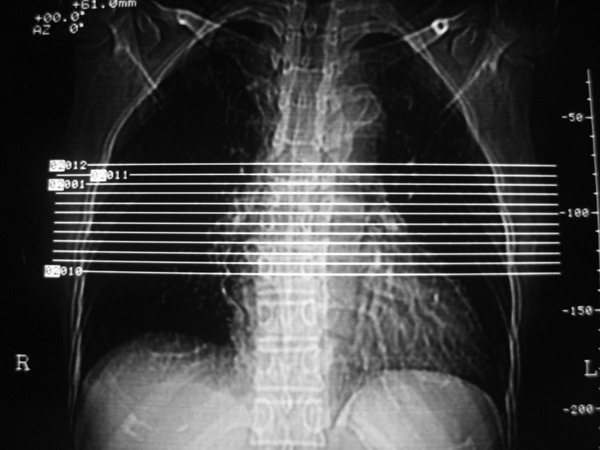

标题: CT6781:胸椎CT,

女,45岁,胸背部疼痛2个月。t6、7胸椎病变。